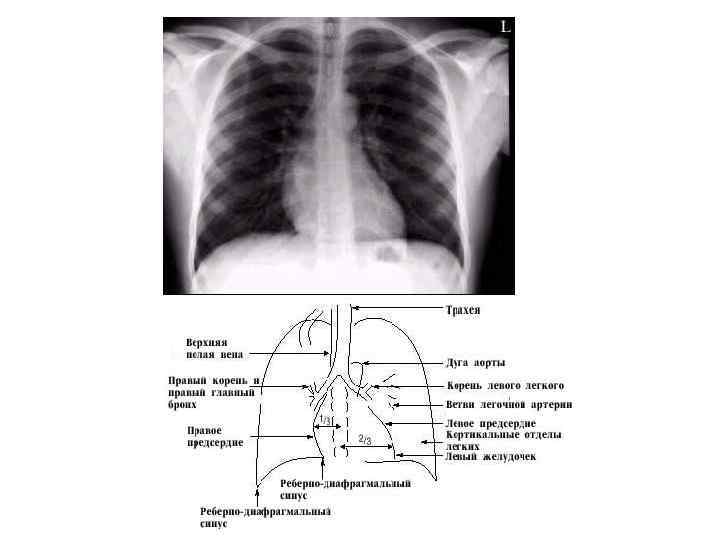

Рентгенография • Рентгеногра фия (англ. projection radiography, plain film radiography, X-ray imaging, roentgenography, Xray study, X-ray filming) — исследование внутренней структуры объектов, которые проецируются при помощи рентгеновских лучей на специальную плёнку или бумагу. Наиболее часто термин относится к медицинскому неинвазивному исследованию, основанному на получении суммационного проекционного изображения анатомических структур организма посредством прохождения через них рентгеновских лучей и регистрации степени ослабления рентгеновского излучения

Рентгенологический метод • Базируется на целом комплексе общих и специальных методик, некоторые из последних сейчас не используются в практической работе, другие- по показаниям. Начинают Рн-исследование с основных, самых простых методик, к которым относятся • Рентгенография и рентгеноскопия